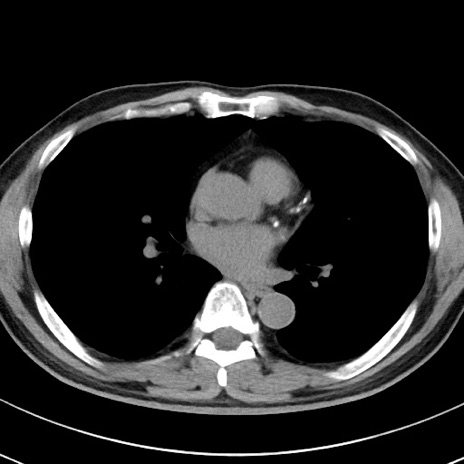

【腹部TIPS】症例29 参考症例 CT(横断像)

症例

70歳代男性